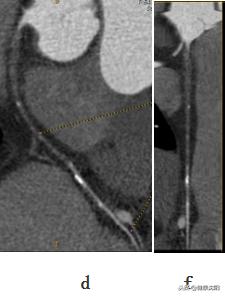

df:显示血管曲面、拉直图像,观察到血管内闭塞及狭窄情况

简单地说就是将不在同一片面的组织或血管重组到一个平面上显示的技术。它能显示血管壁、血管腔内的病变,可以判断有无斑块,斑块的性质,血管与周围组织的关系等等,当VR、MIP发现管腔狭窄或扩张时,可以通过CPR明显病因。探针技术是在CPR拉直血管的基础上,探测感兴趣区域的血管内壁情况的技术。